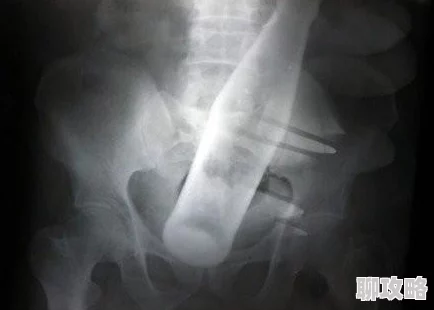

除了作为性癖好外,肛门扩张也具有一定的医疗需求。例如,对于某些患者而言,这项技术可以帮助缓解便秘或其他消化系统问题。医学文献显示,一些医生会建议使用适当的方法进行肛门扩张,以促进排便功能。一位医生提到:“适度的肛门扩张可以帮助放松括约肌,从而改善排便困难。”

此外,对于那些经历过直肠手术或创伤的人来说,进行适当的训练也是恢复过程的一部分。这类患者通常需要通过专业指导来安全地进行此类活动,以避免进一步损伤。因此,在医疗领域内,对这一行为的理解和应用显得尤为重要。